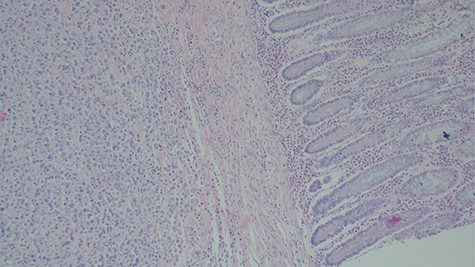

Laboratory investigations revealed a low platelet level of 53 per microliter and hemoglobin level of 10.7 g/dl. Renal profile, white blood count and serum electrolytes were within normal range. Computed tomography intravenous urogram revealed a large heterogeneous mass, measuring 5.5 × 4.5 cm at the right superolateral aspect of the urinary bladder with ipsilateral hydronephrosis and hydroureter. Bone scan study was unremarkable. Urothelial cell carcinoma of the urinary bladder was clinically suggested as the most likely differential diagnosis. Cystoscopy was done under spinal anesthesia, which revealed a solid mass with areas of necrosis at the anterior bladder wall. The biopsy was taken whose histological evaluation revealed a high-grade malignant mesenchymal tumor made up of oval or spindle cells with osteoid formation in many areas of the lesion (Fig. 1). No definite carcinomatous component was appreciated. The tumor was strongly positive for vimentin immunohistochemistry staining (Fig. 2) and negative for cytokeratin 20. Calcified schistosomal ova were also seen (Fig. 3).

Calcified schistosomal ova near or within the tumor (H&E ×400).

A number of risk factors for primary extraskeletal osteosarcoma have been reported in the literature. Radiotherapy, schistosomal infection, trauma, diverticulitis, use of chemotherapy agents such as cyclophosphamide and frequent urinary tract infections have been implicated [1, 6]. Our patient had schistosomiasis (Fig. 3) which might have been the predisposing risk factor.